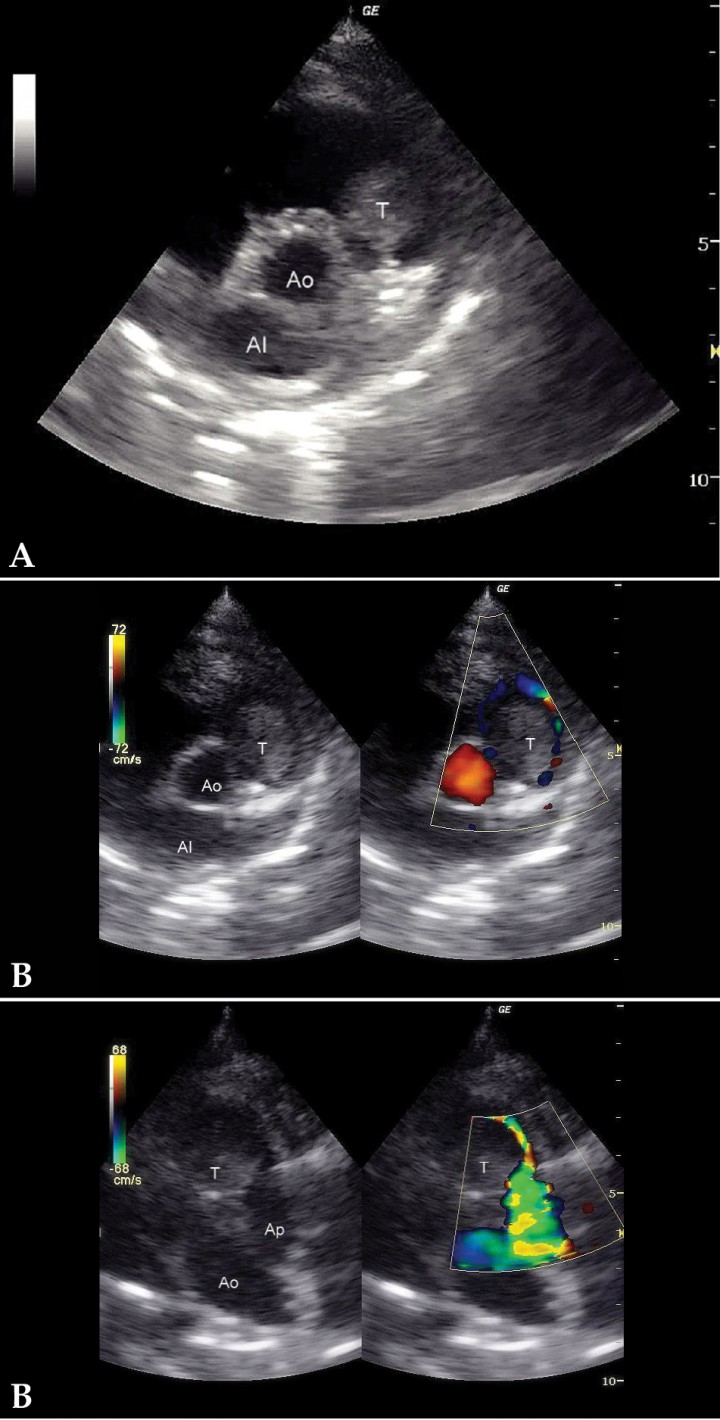

- Dilatación de moderada a severa de cámaras derechas, especialmente atrio derecho (Fig. 3A), con hipertrofia excéntrica del ventrículo derecho.

<p>(A) Corte paraesternal derecho, eje largo, 4 cámaras. Severa dilatación del atrio derecho. (B) Corte paraesternal derecho, eje corto. Presencia de una masa intraluminal en tracto de salida derecho. (C) Corte craneal izquierdo. Presencia de una masa intraluminal en tracto de salida derecho. AD: atrio derecho; AI: atrio izquierdo; VD: ventrículo derecho; VI: ventrículo izquierdo; T: tumor; Ao: aorta; AI: atrio izquierdo; Ap: arteria pulmonar.</p>

(A) Corte paraesternal derecho, eje largo, 4 cámaras. Severa dilatación del atrio derecho. (B) Corte paraesternal derecho, eje corto. Presencia de una masa intraluminal en tracto de salida derecho. (C) Corte craneal izquierdo. Presencia de una masa intraluminal en tracto de salida derecho. AD: atrio derecho; AI: atrio izquierdo; VD: ventrículo derecho; VI: ventrículo izquierdo; T: tumor; Ao: aorta; AI: atrio izquierdo; Ap: arteria pulmonar.

- Presencia de una masa intraluminal de dos por tres centímetros en tracto de salida derecho (Figs. 3B y 3C), que produce una obstrucción al flujo de salida y, por tanto, una reducción del caudal a través de la arteria pulmonar. El flujo laminar de salida a 1,4 m/s se vuelve turbulento a su paso por la masa, a la que rodea claramente (Fig. 4), provocando una aceleración del flujo hasta los 2,9 m/s (Fig. 5).

<p>(A) Corte paraesternal derecho, eje corto. (B) Corte craneal izquierdo. Doppler color con flujo sanguíneo rodeando la masa demostrando obstrucción mecánica del flujo. T: tumor; Ao: aorta; Ap: arteria pulmonar.</p>

(A) Corte paraesternal derecho, eje corto. (B) Corte craneal izquierdo. Doppler color con flujo sanguíneo rodeando la masa demostrando obstrucción mecánica del flujo. T: tumor; Ao: aorta; Ap: arteria pulmonar.